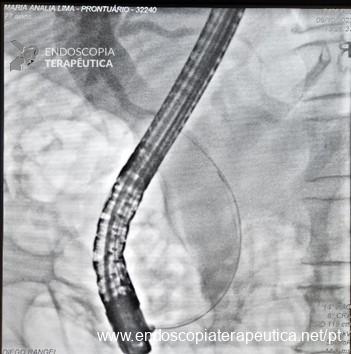

O tratamento, apesar de ainda não bem estabelecido pela literatura, é baseado na sintomatologia e, portanto, sendo recomendada abordagem conservadora em pacientes assintomáticos. A esfincterotomia através de CPRE com ou sem colocação de stent pode ser uma excelente opção terapêutica para pacientes com obstrução da via biliar ou mesmo colangite. Outra opção terapêutica possível é o tratamento cirúrgico através da diverticulectomia, entretanto, com elevada morbimortalidade. No caso ilustrado (Figuras 4-6), a paciente foi tratada com esfincterotomia e esfincteroplastia com balão, seguida de drenagem da via biliar com prótese biliar plástica.

Imagem cedida por Dr. Diego Rangel (BA) e Dra. Sâmara Martins (BA).